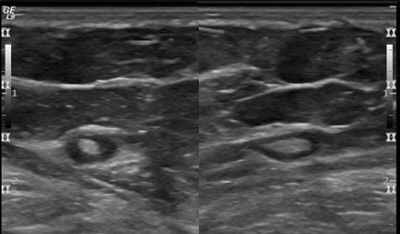

👉A normal axillary lymph node is elliptical in shape (or bean shaped) and has a narrow, symmetrical, hypoechoic cortex surrounding an isoechoic to hyperechoic fatty hilum (Image).

👉The cortex of a normal node is composed largely of lymphatic tissue and fluid-filled cortical sinuses, thus the hypoechoic echogenicity.

👉The hilum contains alternating medullary cords and sinusoids that have innumerable acoustic interfaces, thus the higher degree of echogenicity.